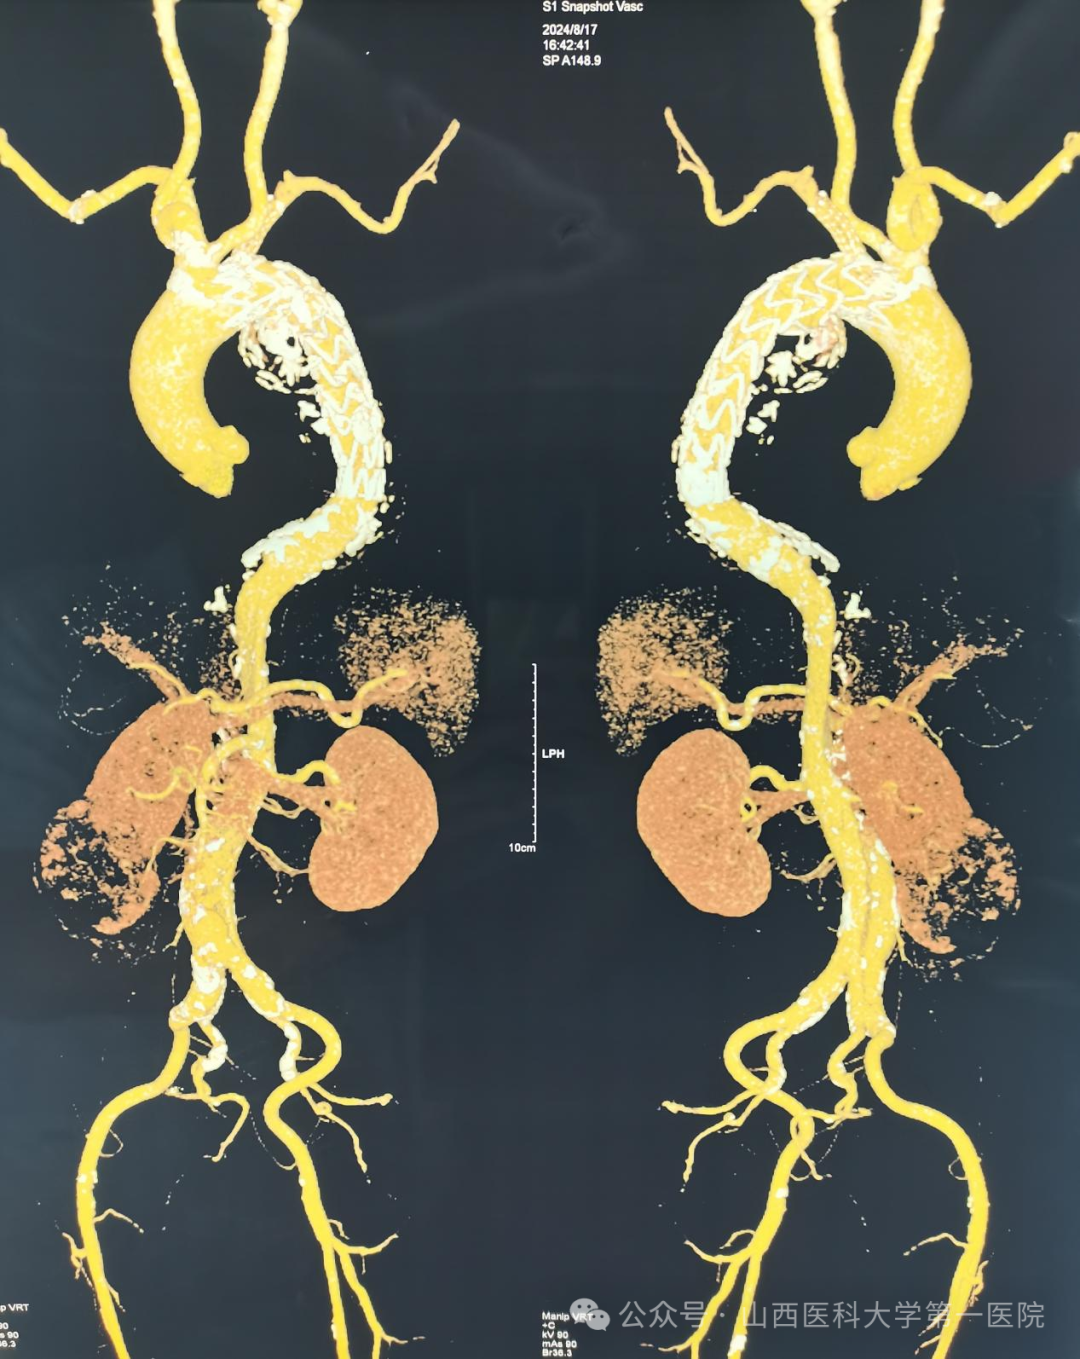

术前血管造影

65岁男性患者因右肾肿瘤合并主动脉夹层、主动脉弓支架植入术后入院。完善相关检查后发现,患者瘤体位于右肾下极,大小约7cm,虽然1月前曾于外院行主动脉弓支架置入术,但检查显示目前存在支架内漏和支架内血栓,且主动脉弓降主动脉移行处至双侧髂总动脉分叉处动脉夹层,主动脉弓、胸、腹主动脉及分支弥漫粥样硬化性病变。同时患者既往合并有高血压、脑梗等基础疾病,病情复杂、凶险、棘手。

主动脉夹层也称为主动脉夹层动脉瘤,指血液通过主动脉壁内膜出现的破口进入动脉管壁形成血肿和夹层,一旦夹层破裂导致大出血,患者往往没有抢救和存活的机会,是一种严重的心血管急症。按照肾肿瘤的常规手术方案,手术过程中必须结扎或阻断肾动脉血管,而主动脉夹层患者由于血管弹性差,脆性高,常规手段处理肾动脉血管风险巨大,且血流动力学改变可能进一步诱发主动脉夹层破裂导致患者死亡。